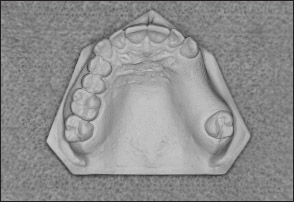

• Kennedy Class II arch: Displays a unilateral edentulous area located posterior to the remaining natural teeth (Figs 1-13 and 1-14).

Fig 1-13 Maxillary Kennedy Class II arch.